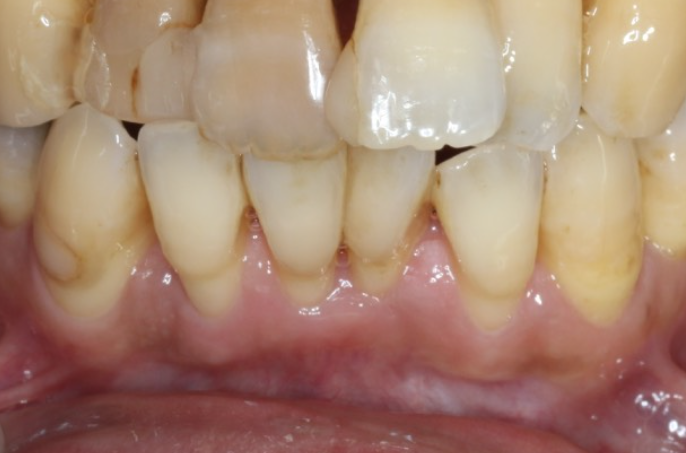

| 患者様データ | 40代 男性 |

| 来院時の主訴 | 「前歯を歯磨きすると痛いし、出血する。」 |

| 医院の診断 | 右上中切歯根尖性歯周炎、歯周病 |

| 通院期間 |

6か月 |

| 来院回数 | 10回 |

| 治療費 | 総額:歯周病治療に関しては保険適用診療。その他:370,000円(税抜) 【内訳】 歯周病治療(歯周病検査・歯磨きや生活習慣指導・歯石取りクリーニング) その他、精密根管治療 70,000円、ファイバーポストコア 20,000円、セラミック治療 140,000円×2 |

| リスクと副作用 | メインテナンスが必要、正しい歯磨き習慣が必要不可欠 |

| ここがこだわりのポイント!☝ | こちらは中等度の歯周病と虫歯を併発されていた患者様です。日々の歯磨き習慣を見直していただき、正しいブラッシング法を身につけたことで健康な歯肉を取り戻しました!短期間での治療を希望されていたので審美的な歯肉ラインの獲得はできませんでしたが、健康的な歯肉を獲得できました。 |